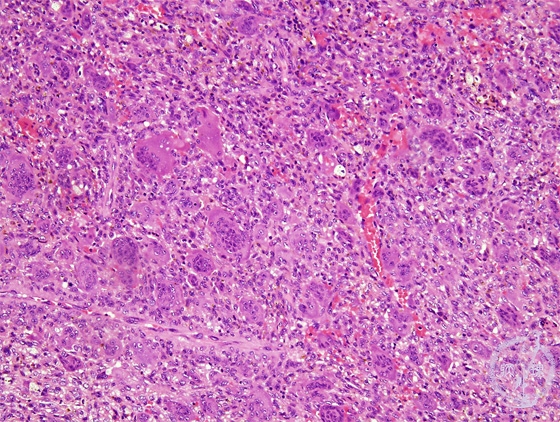

Microscopic view (HE; middle power view): Proliferation of the mixture of mononuclear and multinuclear cells.